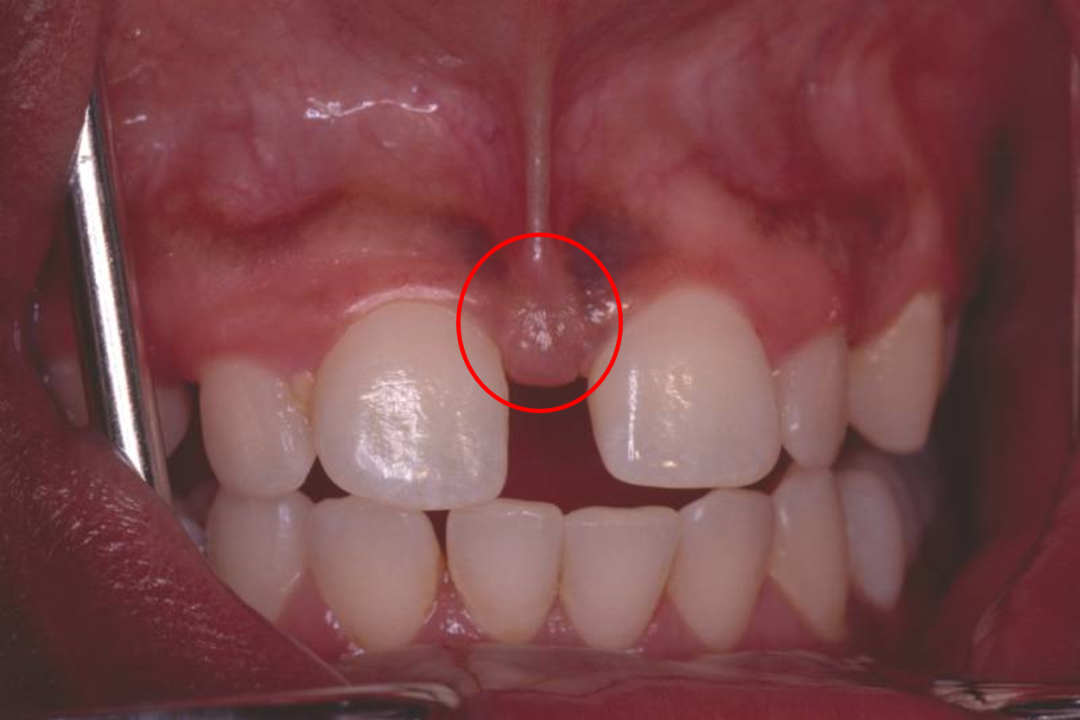

图片

门牙间多生牙

有时候肉眼无法判断,就需要拍摄X线片,辅助检查。

两颗本应该相邻的牙齿之间多了一颗牙齿,中间当然会出现缝隙。若是多生牙导致门牙缝隙,建议拔除多生牙后矫正关闭牙缝。